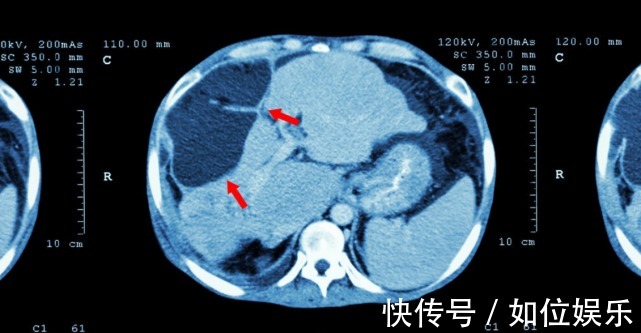

其实对于肝癌的见解,肿瘤科主任给出一个建议:“预防大于治疗”。并且其实肝癌在上身前的一年就会给我们发出“信号”,希望你别忽视了。下面给大家分享一个真实的案例。今年49岁的张先生,是一个电力维修工,在3个月前被确诊肝癌,经过治疗后无果,现已去世。大约在去年,张先生发现自己身上长出了许多大小不一的红色斑点,妻子建议他去检查一下,可是张先生认为,不痛不痒,有什么好检查的。就这样一直拖下去,直到年底,张先生还出现了右腹部疼痛的情况,有时疼的难以入睡,这才来到医院做检查,一查,结果让张先生一家陷入了无尽的悲痛之中。49岁的张先生被确诊为肝癌,并且已经是晚期了。肝内有一个鸭蛋差不多大小的肿瘤,甲胎蛋白460ug/L,医生尽力治疗3个月后,还是因病情严重离世。